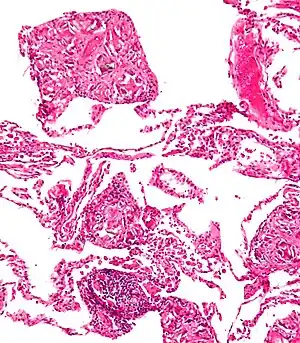

Foreign bodies in the peritoneum eventually become contained in a foreign body granuloma. In the extremely rare case of retained ectopic pregnancy, this forms a lithopedion.